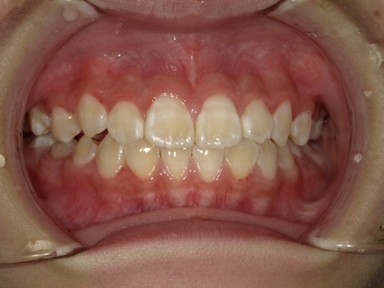

| 主訴 | 前歯が出ているので歯並びを良くしたい。 |

| 治療内容 | 使用装置:- マイオブレース(K1, K2, B1, K3) – 急速拡大装置 ・ワイヤー矯正:上顎前歯部(2-2)のみに2か月間使用 ・抜歯:なし |

| 治療費 | 550,000円(税込み) |

| 治療期間 | 2020年2月~2023年1月(永久歯列完成まで観察) |

| 治療回数 | 25回 |

| 想定されたリスク | 全額ワイヤー治療になる可能性とそれに伴う歯根吸収のリスクがありました。 |

かみ合わせが非常に深く、下顎の成長を妨げておりました。扁桃腺の肥大が一因として考えられたため切除の提案をしました。マイオブレースを中心に、短期間のワイヤー治療でかみ合わせも健康面も良好になったかと思います。